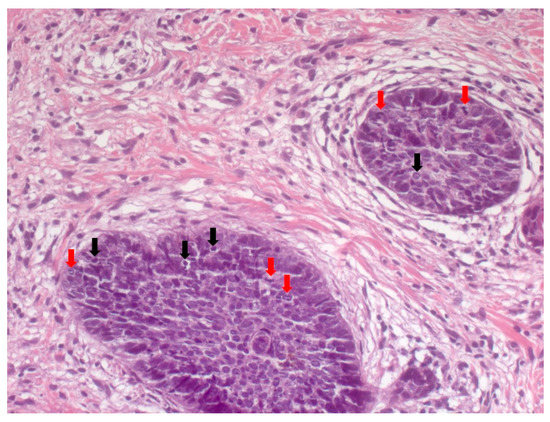

4. Histopathological Features of BCC

- Paolino, G.; Donati, M.; Didona, D.; Mercuri, S.R.; Cantisani, C. Histology of Non-Melanoma Skin Cancers: An Update. Biomedicines 2017, 5, 71. [Google Scholar] [CrossRef]

- Crowson, A.N. Basal cell carcinoma: Biology, morphology and clinical implications. Mod. Pathol. 2006, 19 (Suppl. 2), S127–S147. [Google Scholar] [CrossRef] [PubMed]